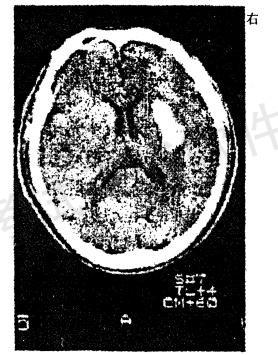

男性,56岁。高血压患者。旅游登山中突然左侧 肢体发麻、乏力。急送医院,摄头颅CT片如图

CT影像中描述病灶呈A.高信号区

B.低信号区